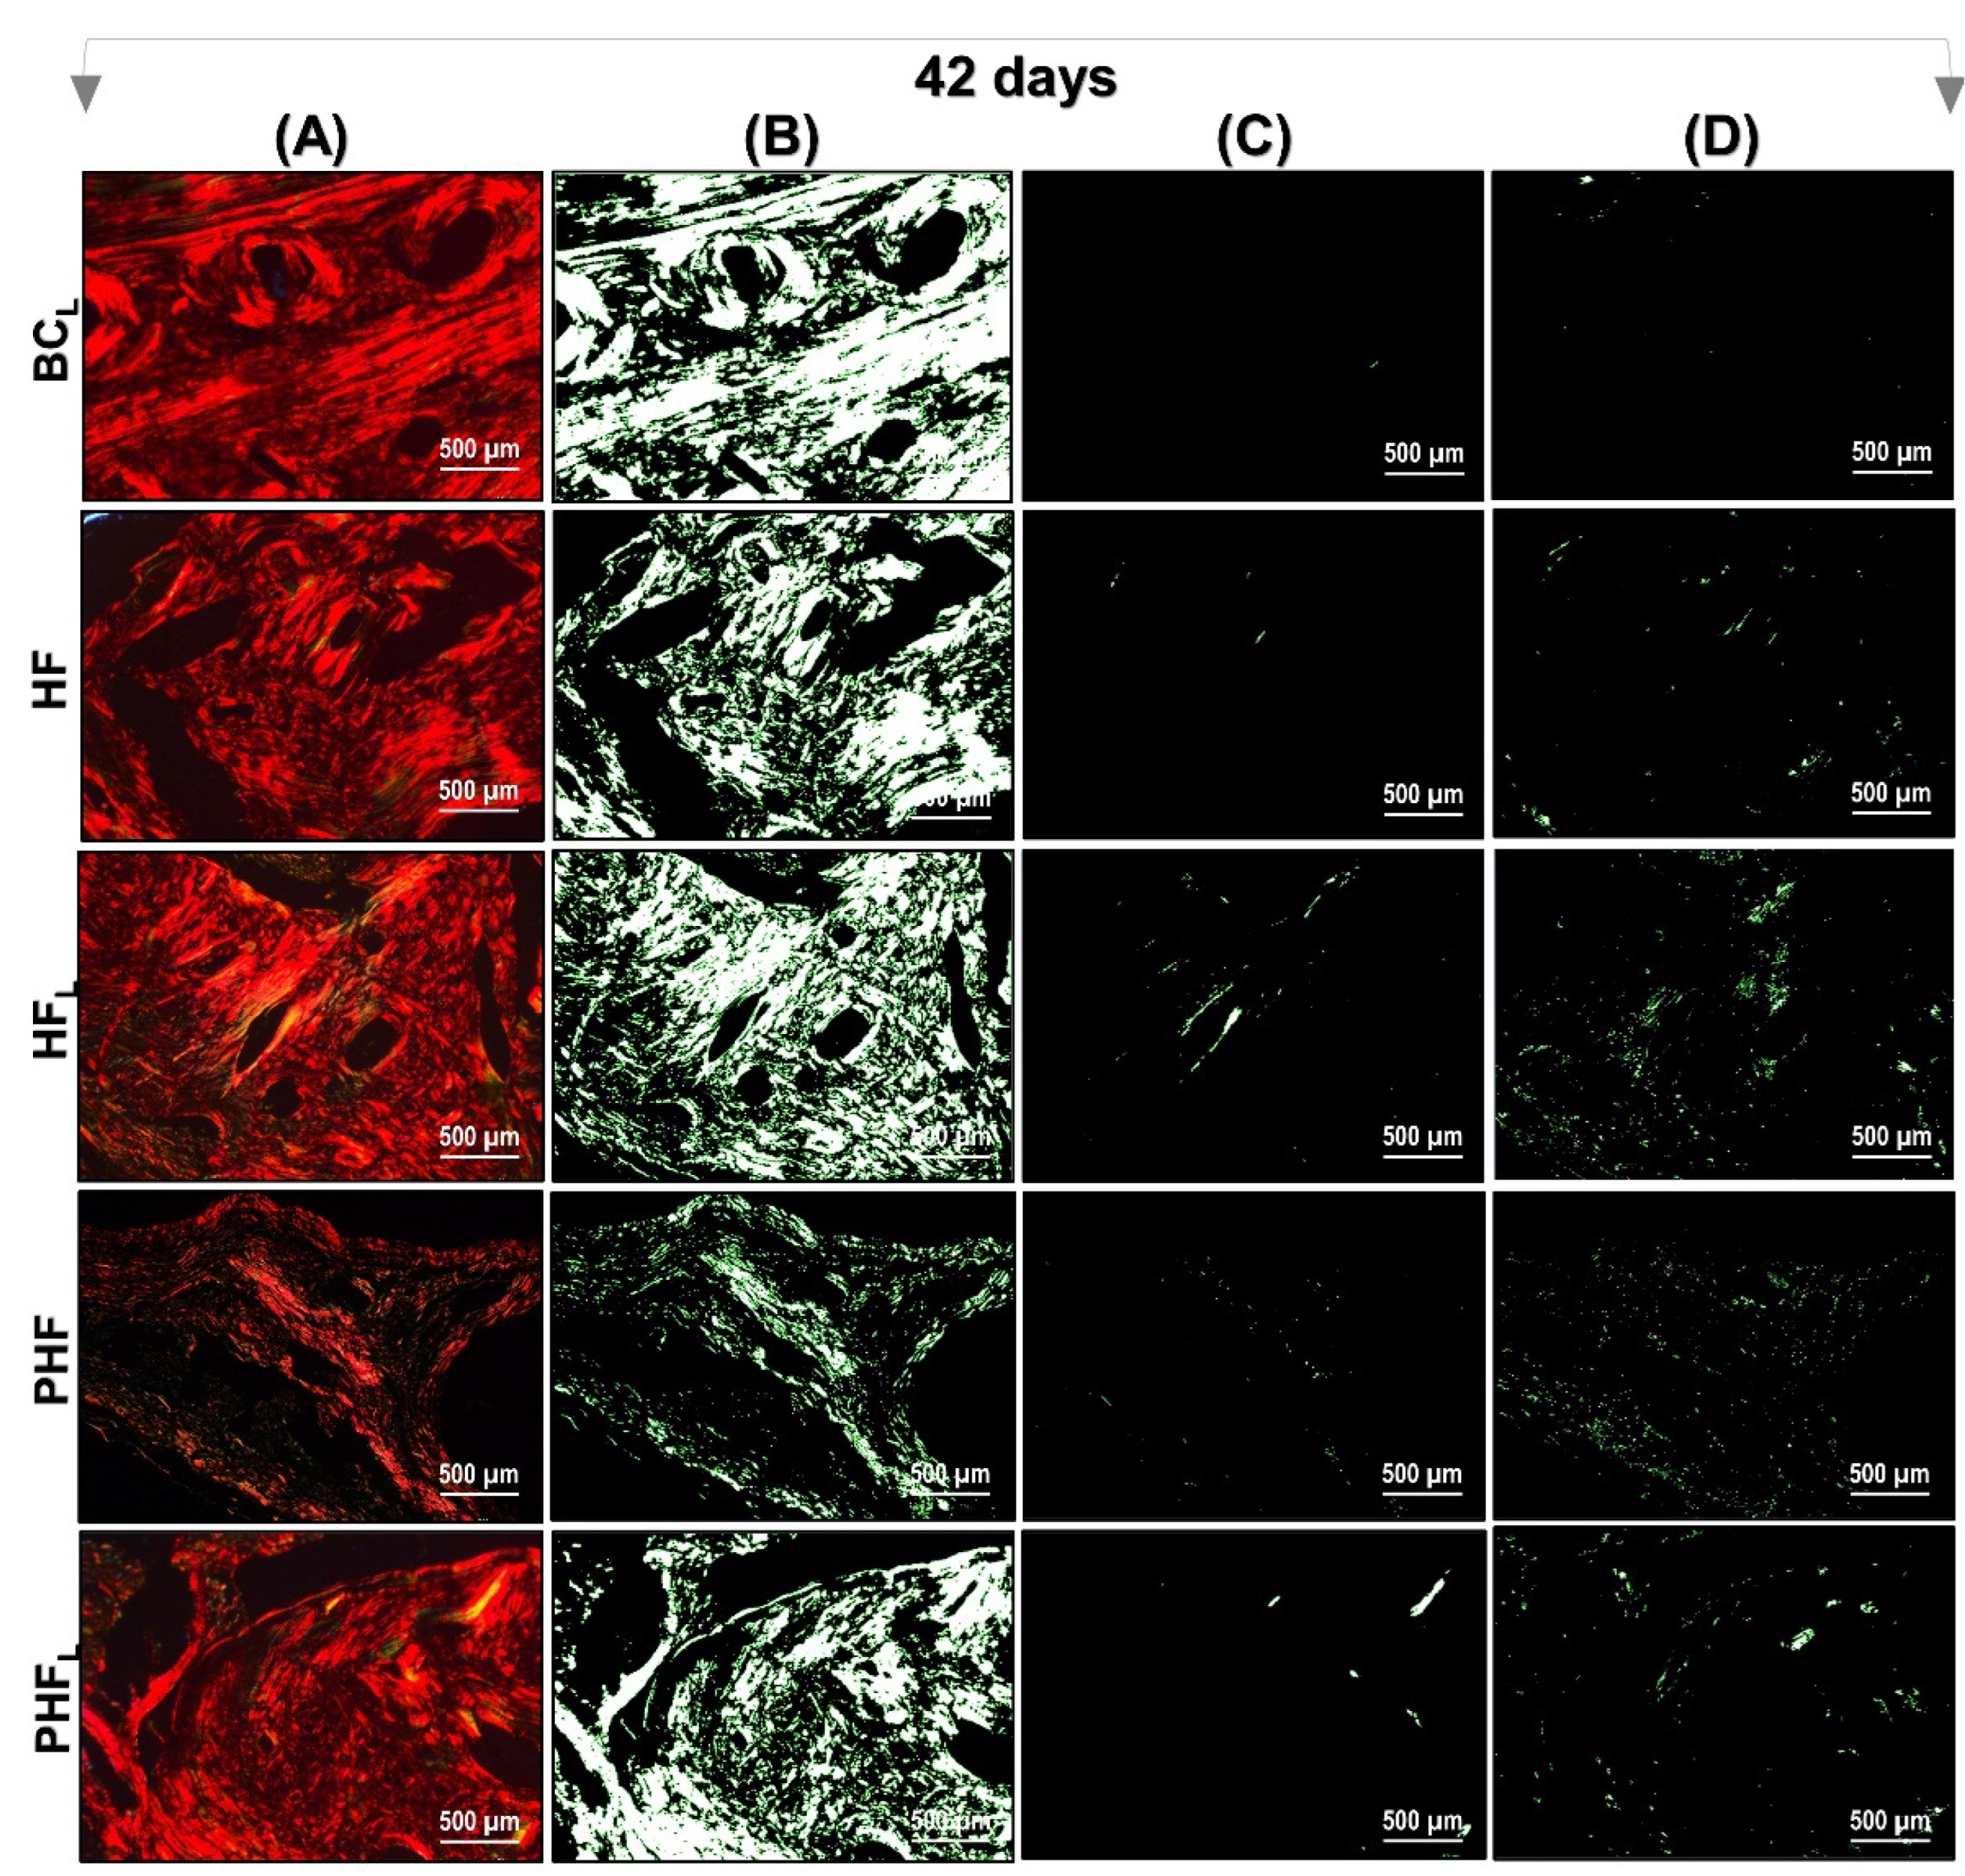

2.3. Birefringence Analysis of Collagen Fibers in Bone Neoformation

4.10. Birefringence Analysis of Collagen Content of Bone Defects